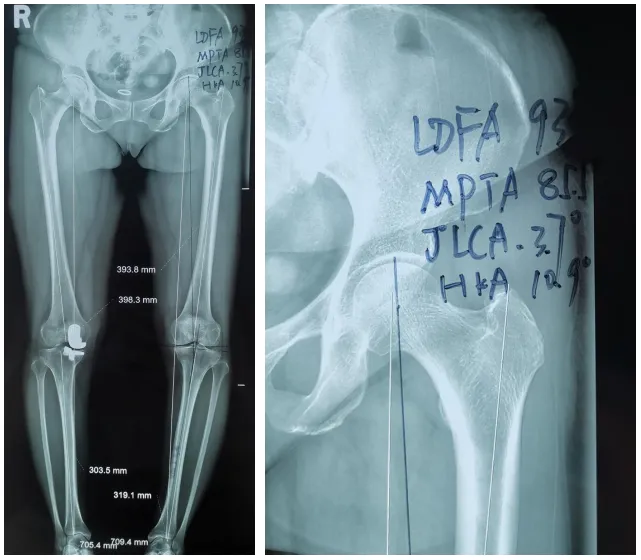

术前下肢全长片及测量结果

骨三科副主任李兵接诊后,经过影像学检查及测量,发现侯女士左膝关节软骨并未达到全层磨损,而且伴有明显的膝内翻畸形(“O”型腿),经过与患者沟通,决定行“左侧股骨髁上截骨术”(DFO)。